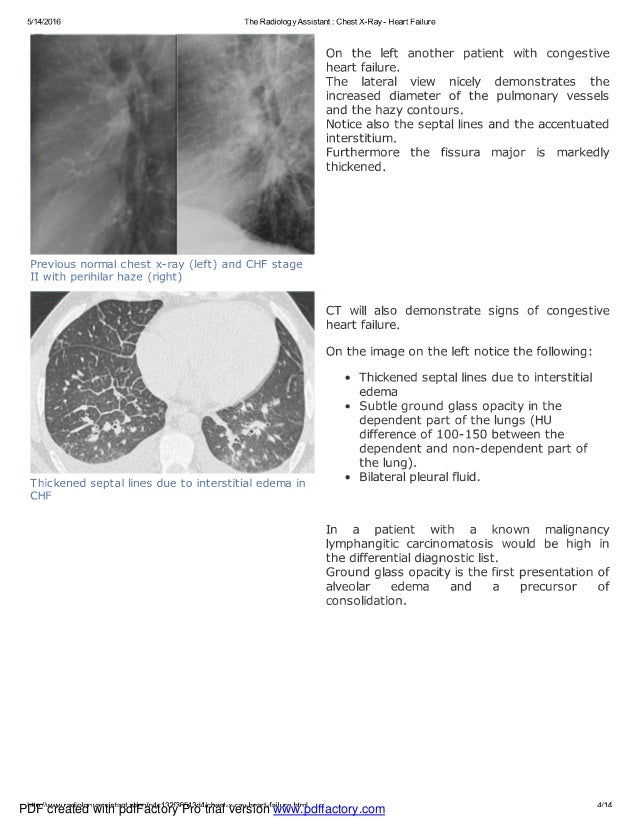

From radiologyassistant.nl

The Radiology Assistant Chest XRay Heart Failure Abcde Chest X Ray Heart Failure Kerley b lines (interstitial oedema) chest x ray examination. The chest x ray examination has an important role in the routine investigation of patients. Abcde Chest X Ray Heart Failure.

The Radiology Assistant Chest XRay Heart Failure Abcde Chest X Ray Heart Failure The chest x ray examination has an important role in the routine investigation of patients. Kerley b lines (interstitial oedema) chest x ray examination. Abcde Chest X Ray Heart Failure.

The Radiology Assistant Chest XRay Heart Failure Abcde Chest X Ray Heart Failure Kerley b lines (interstitial oedema) The chest x ray examination has an important role in the routine investigation of patients. chest x ray examination. Abcde Chest X Ray Heart Failure.

The Radiology Assistant Chest XRay Heart Failure Abcde Chest X Ray Heart Failure chest x ray examination. Kerley b lines (interstitial oedema) The chest x ray examination has an important role in the routine investigation of patients. Abcde Chest X Ray Heart Failure.